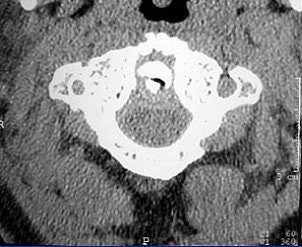

![]() ![]() |

The 0.5-mm slices offer fine bone detail, but pay a price on the soft-tissue images in terms of soft-tissue differentiation. Whereas the thicker (5-mm) slices fail to show the bone detail of the fracture well, but possess greater contrast resolution on the soft-tissue window to differentiate spinal cord from surrounding spinal fluid.